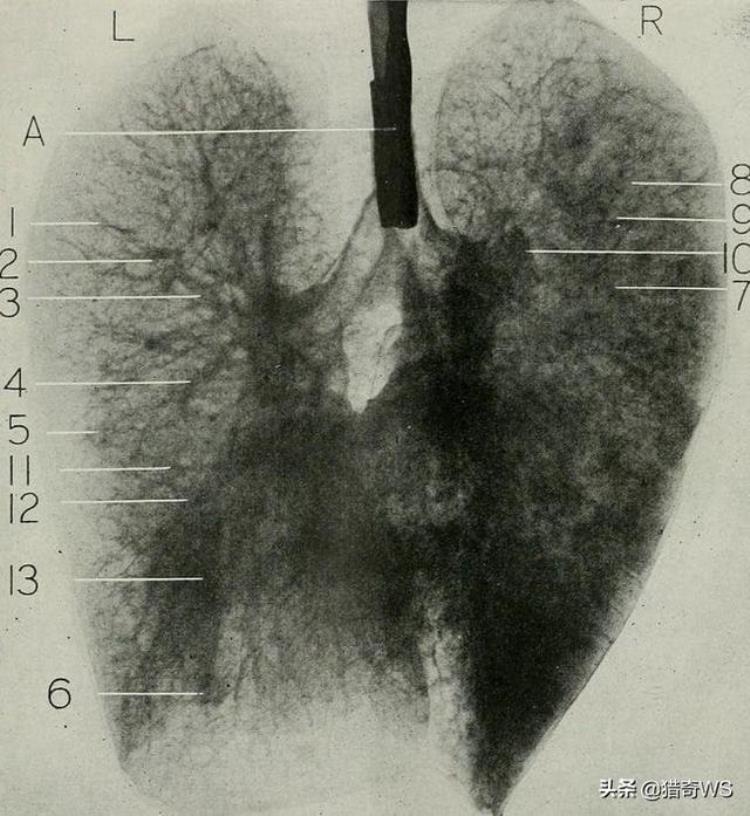

美国飞行员泰迪蓬茨卡降落后被匕首割伤。诊疗结果报告显示,创口很深。由于他们觉得仅仅是在医院进行医治,也没有反抗。终究,戴着口罩,衣着白长衫的医师,把他们的肺切除了。

美国飞行员泰迪蓬茨卡是第一个在九州大学开展药物试验的人。 那边的一位医师根据切除一个人的全部肺来检测手术治疗对呼吸道的危害。

他进入手术室后,肺脏被取下,手术缝合创口,如同啥都没有少一样。 手术中,庞茨卡服食镇定剂,肺取下后防护口罩被取下。 一份实验结果报告显示,取下防护口罩后,受害人逐渐摇晃,医师托里瑟在乳房开了一个新口子,用手终止了心血管的颤动。